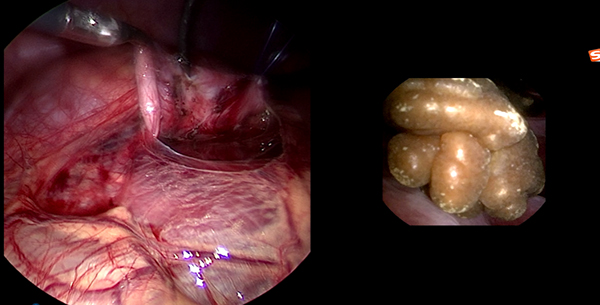

一名14岁男性青少年因活动后血尿检查发现右肾积水并右肾结石,进一步检查发现患儿右肾积水的原因是肾盂输尿管连接部梗阻所致。由于患儿肾盂输尿管连接部狭窄,常规输尿管软镜碎石无法实施。由于结石位于右肾下盏,盏颈狭窄、腹腔镜下无法直接取石。经小儿泌尿外科讨论后,决定在患儿行腹腔镜肾盂成形术的同时联合输尿管软镜进行右肾下盏激光碎石。手术在吴荣德教授指导下,由刘伟主任医师、杜国强副主任医师等共同完成。经腹腔镜探查发现患儿肾盂输尿管连接部狭窄,狭窄段长0.5cm,肾盂扩张积水。于肾盂切开约0.5cm,自腹壁置入输尿管软镜经肾盂切口进入,在下盏内见一大小约1.0×0.8cm黄褐色桑葚样结石,经输尿管软镜置入钬激光光纤予以碎石。碎石后取出大块结石颗粒,吸净碎屑后行腹腔镜下右肾盂成形术。患儿术后恢复良好,顺利出院。后期患儿规律复查,未再出现血尿、腹痛等不适症状。